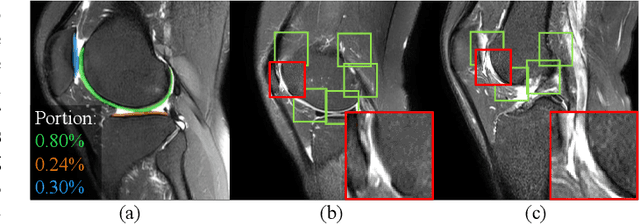

Abstract:Knee osteoarthritis (OA) is the most common osteoarthritis and a leading cause of disability. Cartilage defects are regarded as major manifestations of knee OA, which are visible by magnetic resonance imaging (MRI). Thus early detection and assessment for knee cartilage defects are important for protecting patients from knee OA. In this way, many attempts have been made on knee cartilage defect assessment by applying convolutional neural networks (CNNs) to knee MRI. However, the physiologic characteristics of the cartilage may hinder such efforts: the cartilage is a thin curved layer, implying that only a small portion of voxels in knee MRI can contribute to the cartilage defect assessment; heterogeneous scanning protocols further challenge the feasibility of the CNNs in clinical practice; the CNN-based knee cartilage evaluation results lack interpretability. To address these challenges, we model the cartilages structure and appearance from knee MRI into a graph representation, which is capable of handling highly diverse clinical data. Then, guided by the cartilage graph representation, we design a non-Euclidean deep learning network with the self-attention mechanism, to extract cartilage features in the local and global, and to derive the final assessment with a visualized result. Our comprehensive experiments show that the proposed method yields superior performance in knee cartilage defect assessment, plus its convenient 3D visualization for interpretability.